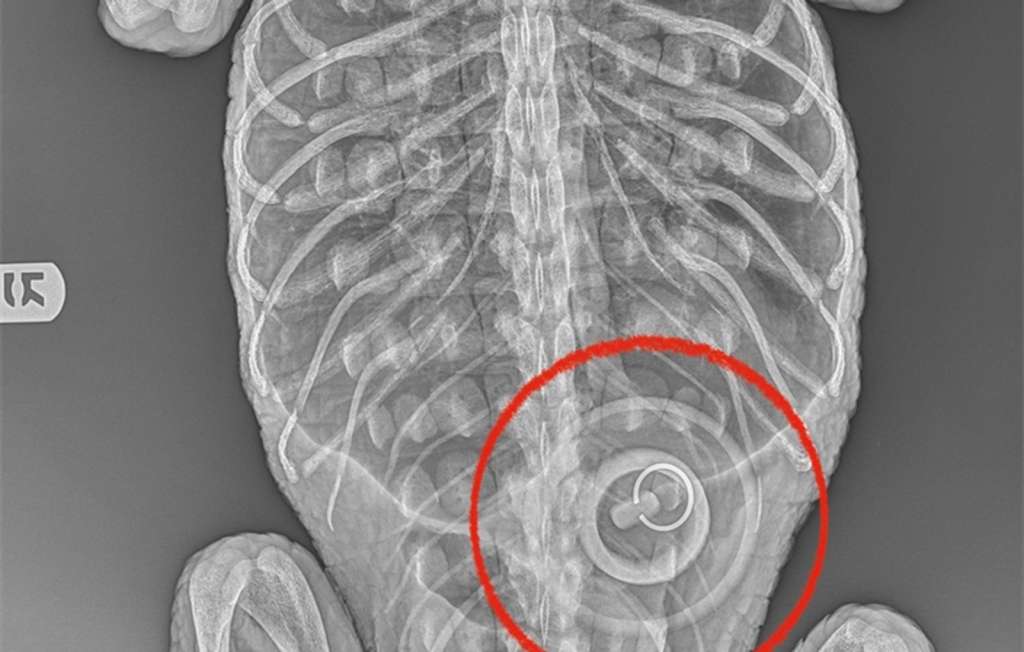

Since then, the reptile, found emaciated and suffering from the cold weather, has been cared for by the city’s Bronx Zoo. In a blog post published Wednesday, the zoo said X-rays revealed the female alligator had ingested an approximately 4-inch-wide bathtub stopper.

The zoo said it won’t immediately be removing the stopper because the gator is “in too weakened a condition.”